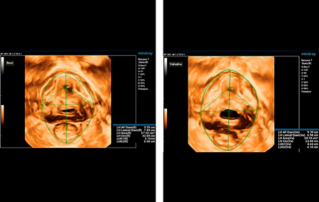

?? ?? ??? ?????(Endocavity volume convex array transducer)(DE10-3WU, Resona 7, ?????)? ??? ??? ???, ??? ?? 1/3 ?? ? ??(anterior vaginal wall)? ???? 18x14 mm ??? ?? ??(an ovoid-shaped formation) with a parietal fine suspension, ????? ??? ???? ??(non-displaced), ????,? CDI ??? ?? ?? ???? ????????. 3D ??? -? ??? ? ??(hyperechoic septa)? ?? ???? ??? ?? ??.

?? ??? ?? ???(Volumetric reconstruction)? ??? ??? ?? ??? ?? ??? ??? ? ??? ?? ??????? ??? ??? ??? ???.